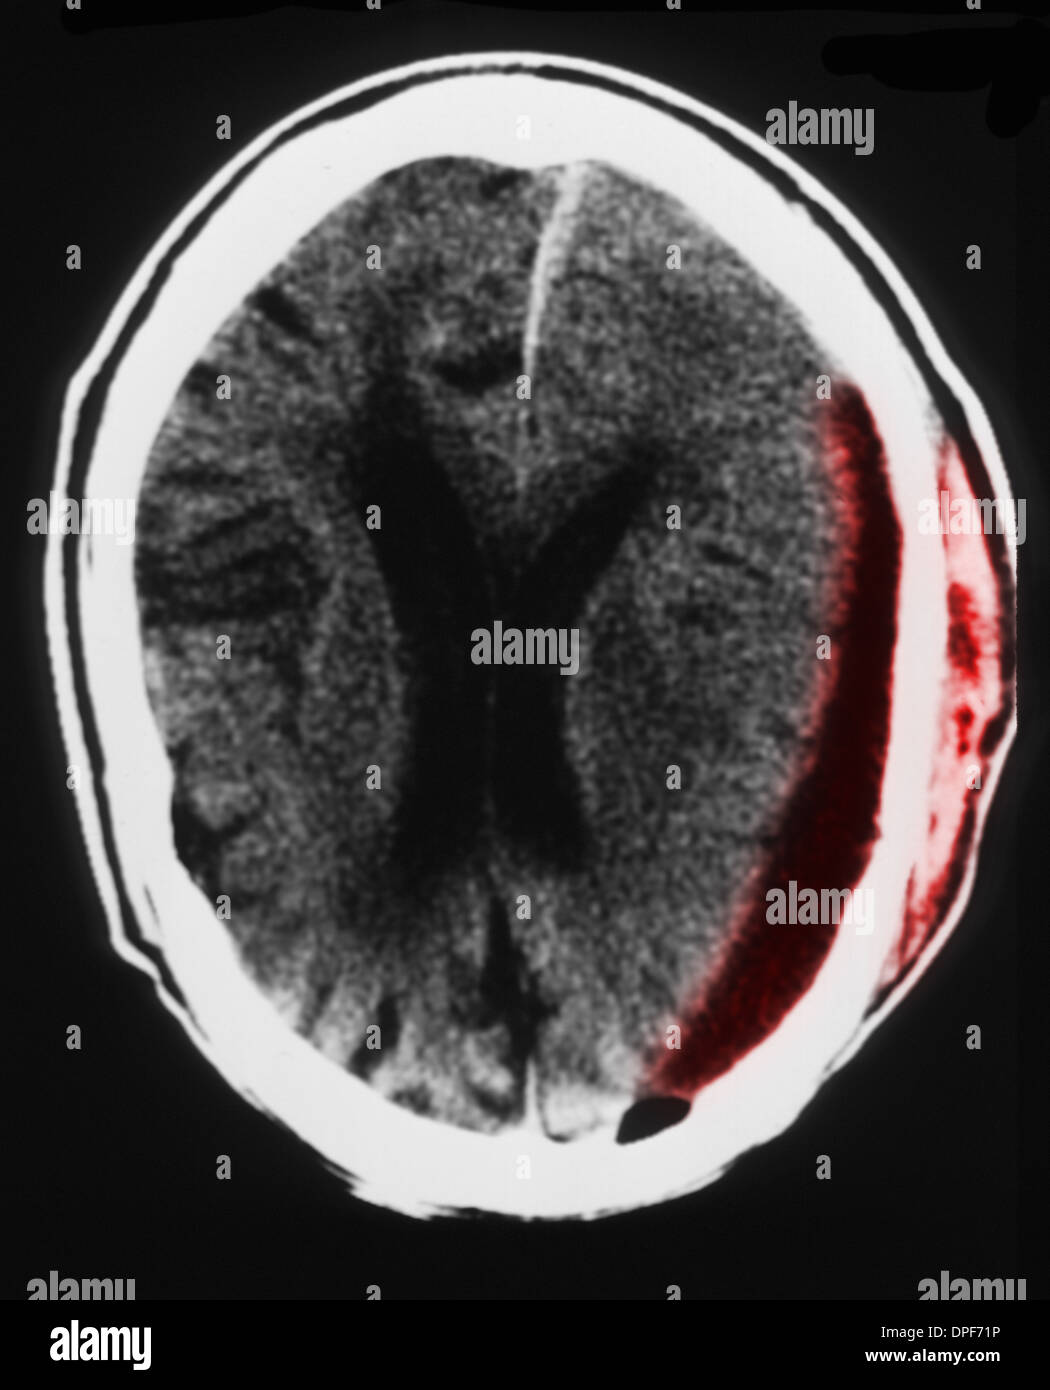

Scansione Tc Della Testa Con L Ematoma Subdurale Foto Stock Alamy

Scansione Tc Della Testa Che Mostra Un L Ematoma Subdurale Foto Stock Alamy

Scansione Tc Del Cervello Che Mostra L Ematoma Subdurale Foto Stock Alamy

Ct Scan Mostra Un L Ematoma Subdurale Foto Stock Alamy